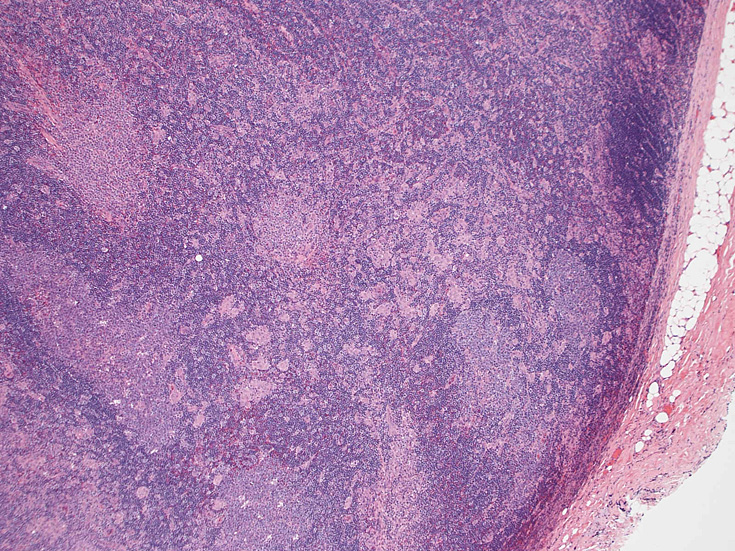

リンパ節病理組織所見

通常傍濾胞領域に小型, 不整形の類上皮細胞肉芽腫が多数形成されている。この症例では慢性炎症を伴い線維性に肥厚した皮膜直下にも多くの肉芽腫病変が散在する。Piringer型リンパ節炎と呼ばれる。

リンパ節病変にトキソプラズマ嚢子は確認できないことがほとんど

皮質から傍皮質に肉芽腫が散在大小不整な肉芽腫looseな肉芽腫皮膜下にも肉芽腫あり